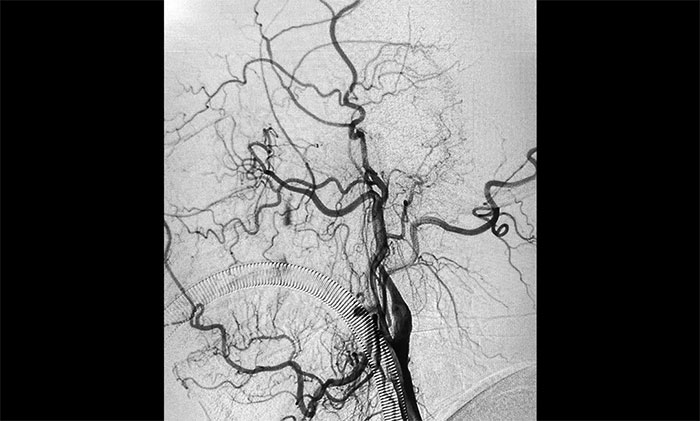

▲術(shù)前DSA影像:左側(cè)頸內(nèi)動(dòng)脈眼動(dòng)脈段以遠(yuǎn)閉塞

術(shù)中腦血管造影可見:左側(cè)頸內(nèi)動(dòng)脈眼動(dòng)脈段以遠(yuǎn)閉塞……余血管未見明顯異常。張琪博士在劉春、周林華、李喆醫(yī)生協(xié)助下,通過右側(cè)股動(dòng)脈穿刺,將微導(dǎo)管、微導(dǎo)絲送達(dá)左側(cè)大腦中動(dòng)脈M1段,經(jīng)多次抽吸+支架拉栓,順利取出血栓。造影顯示,頸內(nèi)動(dòng)脈眼動(dòng)脈段血流恢復(fù)。